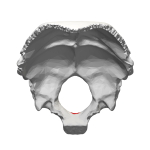

| Skull seen from below. The hole through which the medulla (shown in red) is passing is foramen magnum. |

| Occipital bone inner surface (basion shown in red) |